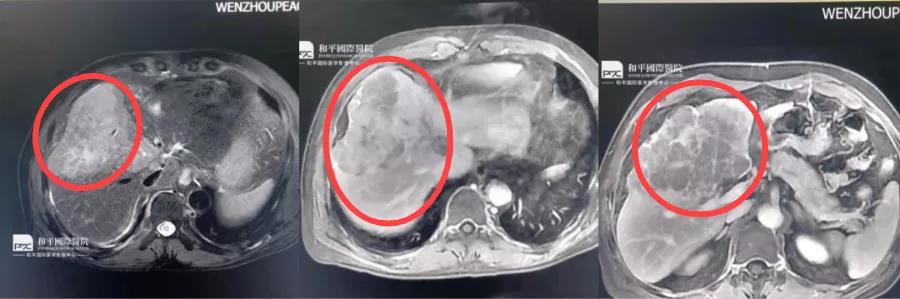

是當(dāng)時(shí)的醫(yī)生推薦的,他說(shuō)和平(和平國(guó)際醫(yī)院)這方面的手術(shù)很好,讓我來(lái)找曾其強(qiáng)醫(yī)生。...